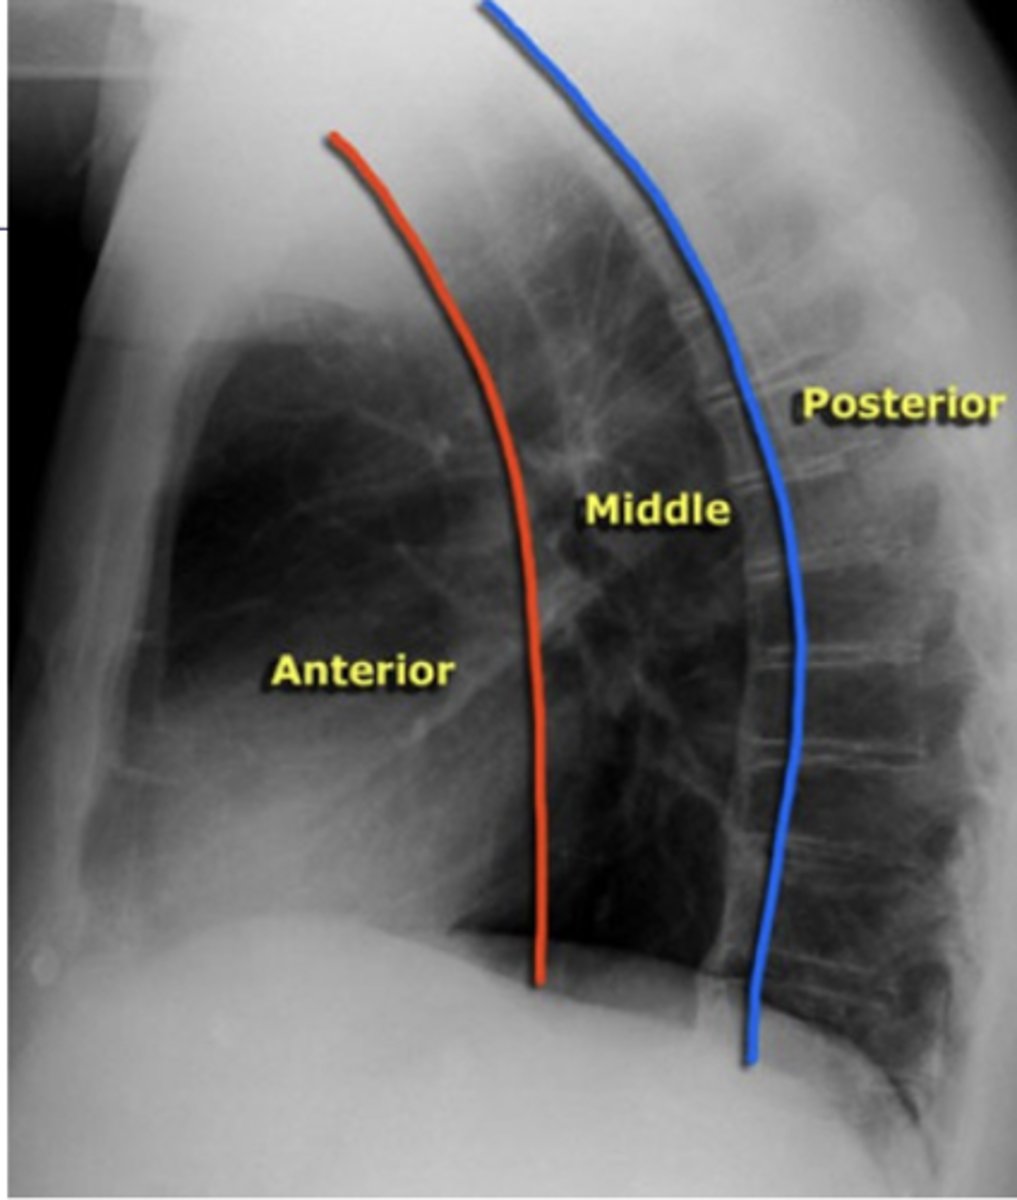

ascending aorta, aortic knob, heart, lymph nodes, thyroid, and thymus

What structures are located in the anterior mediastinal compartment?

<p>What structures are located in the anterior mediastinal compartment?</p>

esophagus, trachea, lymph nodes, and aortic arch

What structures are located in the middle mediastinal compartment?

<p>What structures are located in the middle mediastinal compartment?</p>

descending aorta, lymph nodes, spinal nerves, and vertebral bodies.

What structures are located in the posterior mediastinal compartment?

<p>What structures are located in the posterior mediastinal compartment?</p>